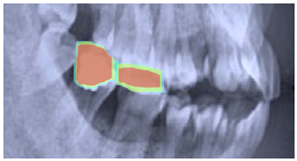

2.3. ROI Identification, YOLO-UNet-Based

3. Results

3.3. Results Obtained from 2D Lateral Cephalogram Analysis Applying AI Techniques